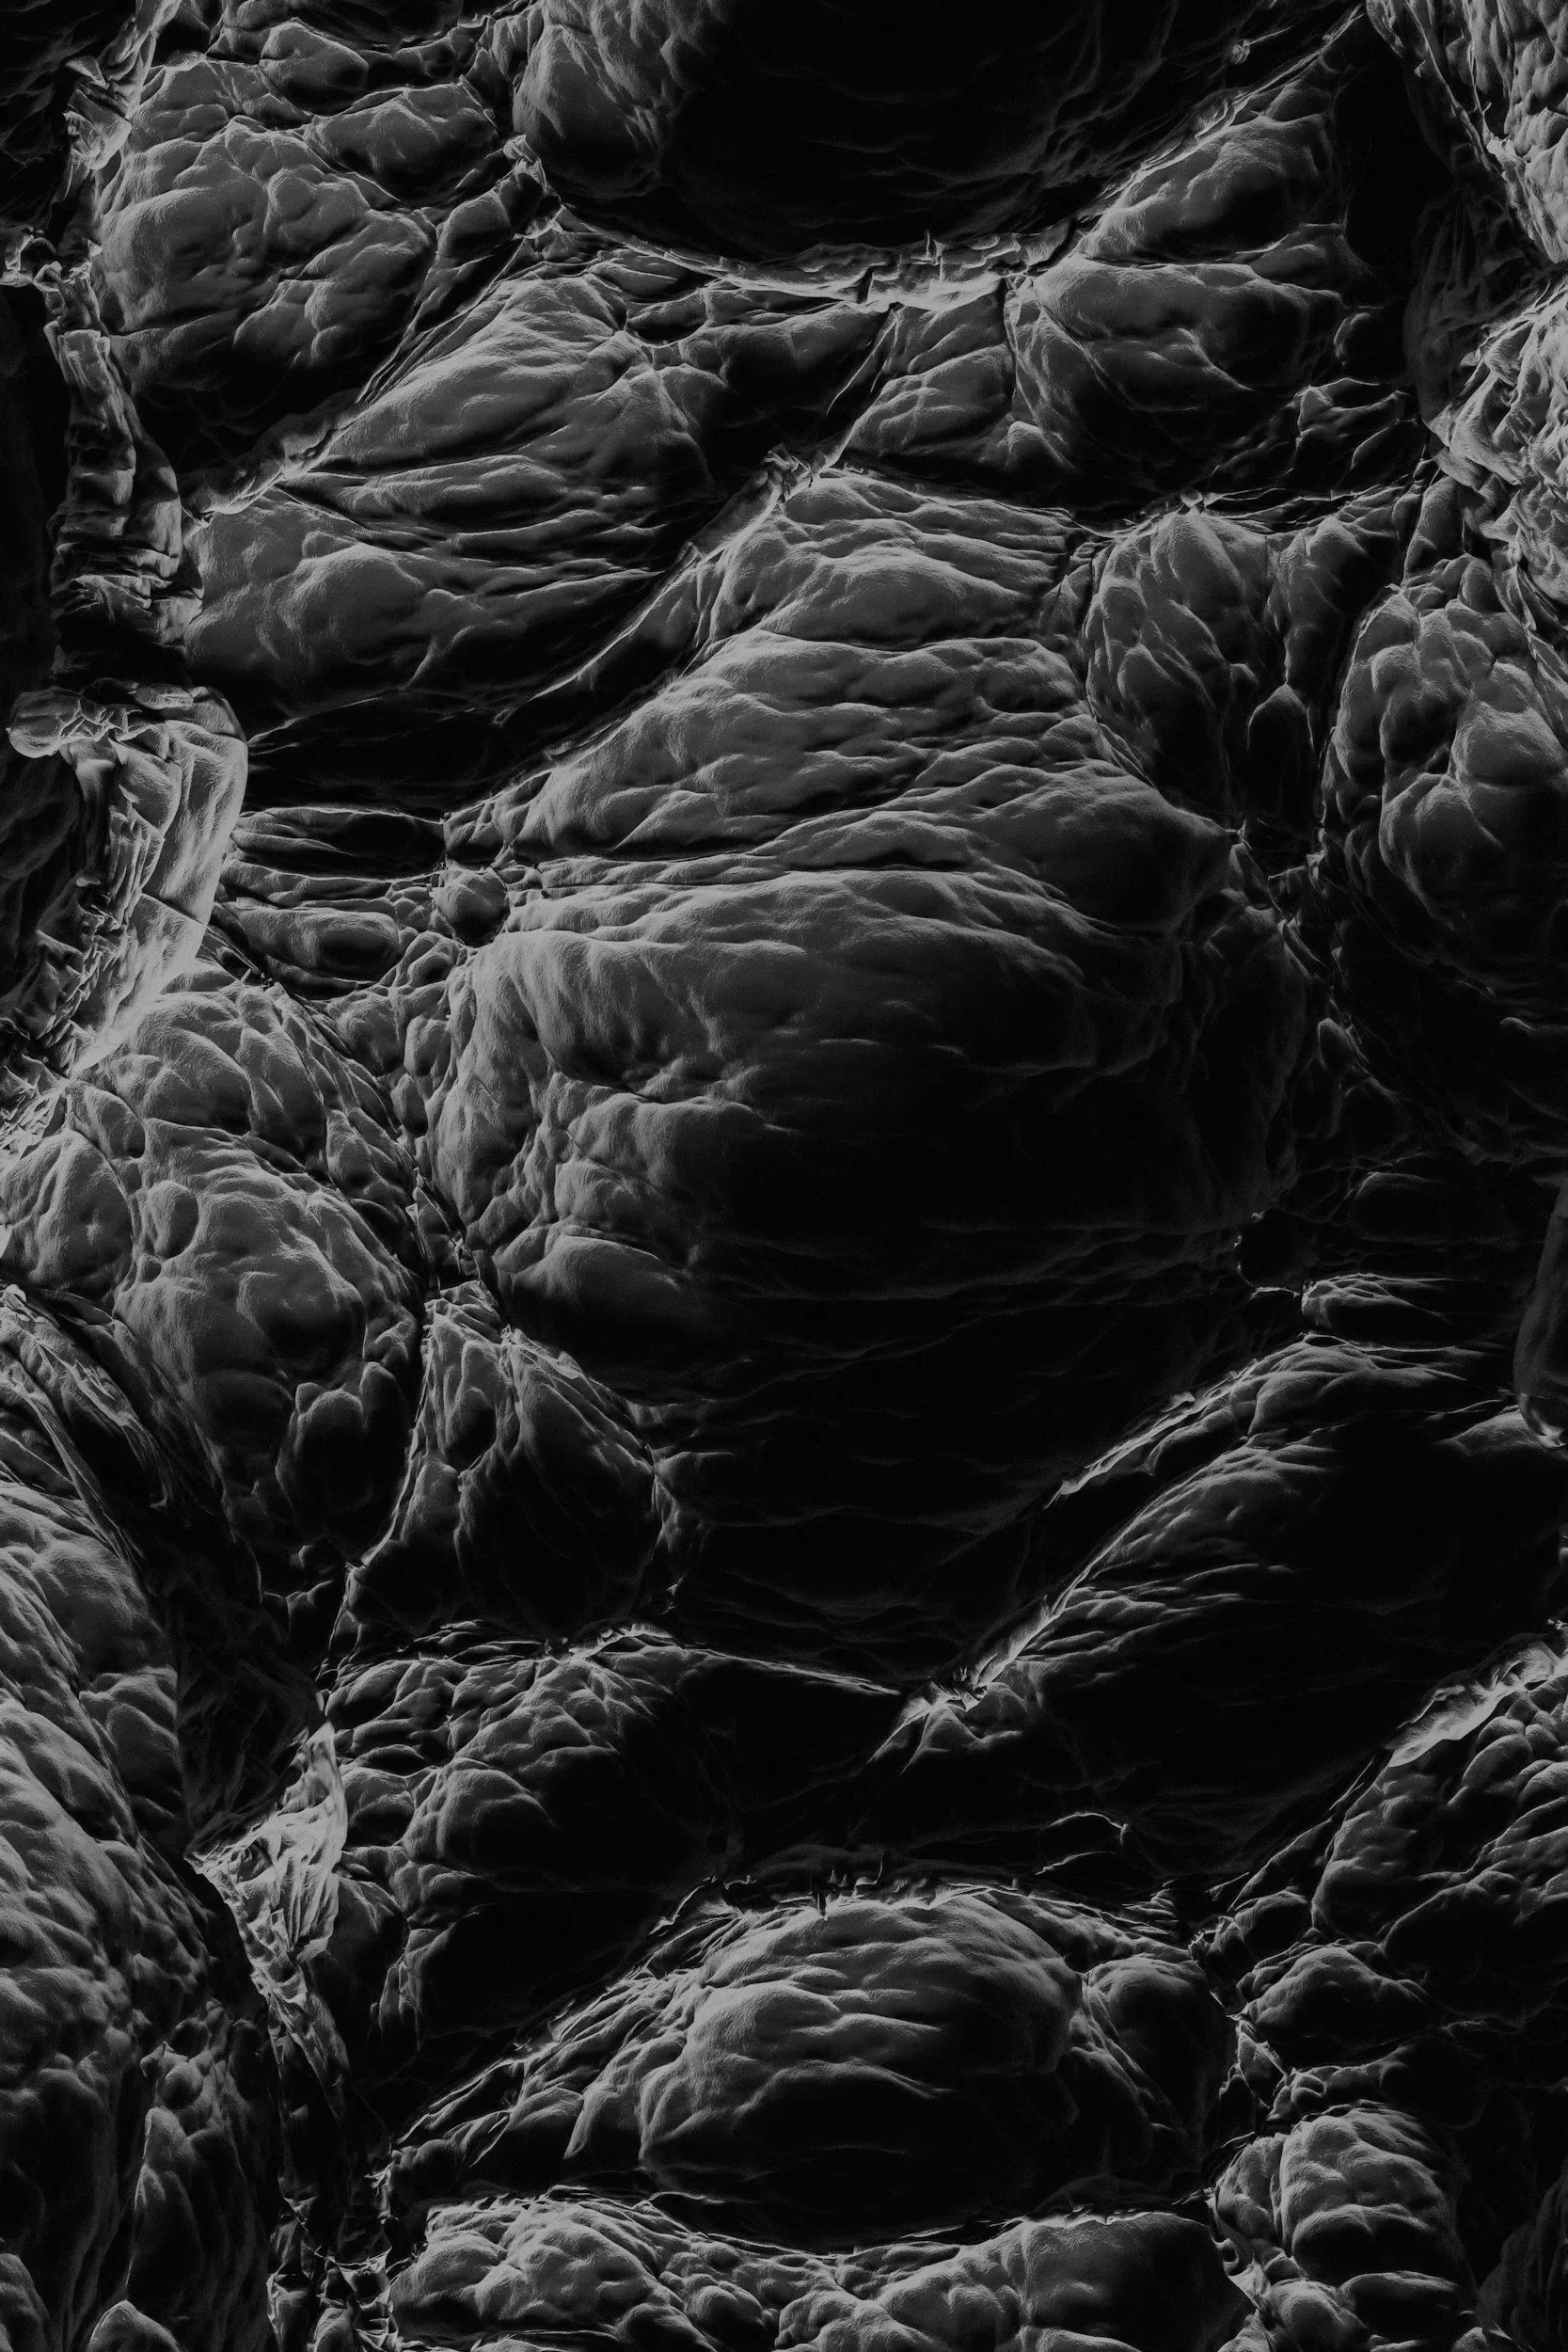

Advantages of the Decellularized Muscle Matrix

Our patent-pending Decellularized Muscle Matrix (DMM) recreates muscle’s natural extracellular environment, providing the structural and chemical cues necessary for healing.

Remove cells, keep structure

Donor muscle tissue is processed to strip away all living cells, leaving behind the extracellular matrix — a natural scaffold made of proteins like collagen, laminin, and fibronectin.

Skeletal muscle is unique: Aligned fibers, satellite stem cells, and neuromuscular junctions allow for extraordinary regeneration. But in severe injuries, the muscle's capacity to regenerate is lost. The components of Sarcogenics’ Decullarized Muscle Matrix began in an academic laboratory and include:

Decellularized scaffold: A whole-muscle derived extracellular matrix stripped of immunogenic cells while preserving pro-regenerative architecture.